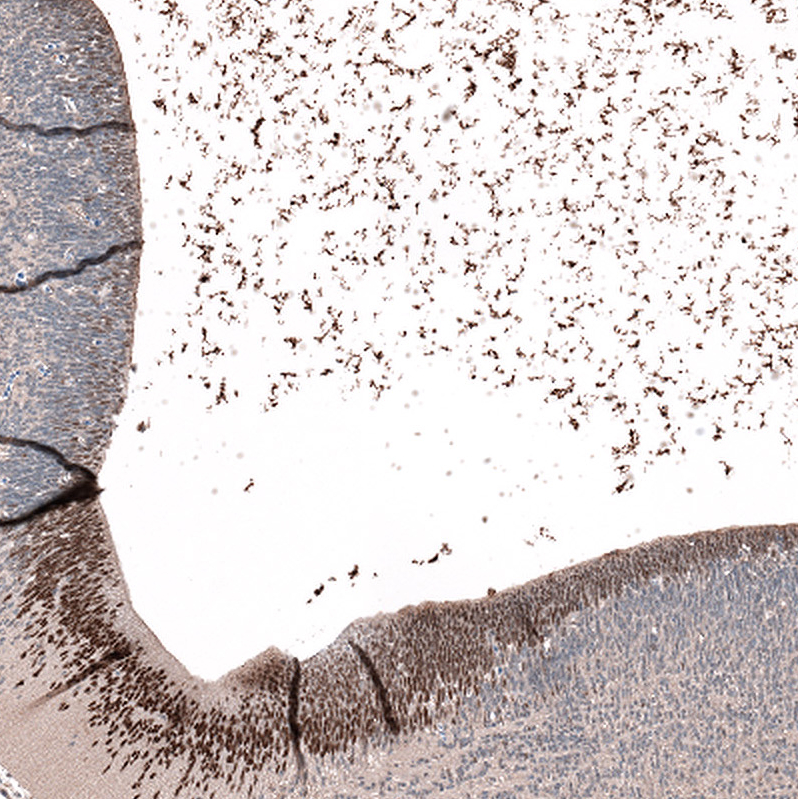

Immunohistochemistry analysis in human testis and endometrium tissues using HPA050527 antibody. Corresponding RFX4 RNA-seq data are presented for the same tissues.